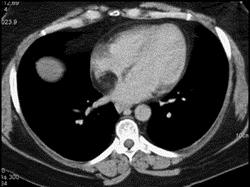

问题 女性,40岁,活动后心慌一年余,彩超发现左心房有异常回声,CT检查如图所示,应考虑为 ( )

选项 A、正常左心房 B、左心房脂肪瘤 C、左心房血栓 D、左心房脂肪浸润 E、左心房粘液瘤

答案 B